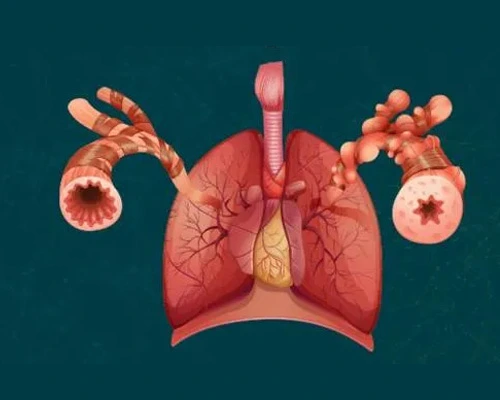

COPD Treatment

Dr. Siddhesh Bharadi offers expert diagnosis and treatment for Chronic Obstructive Pulmonary Disease (COPD), helping patients manage symptoms like chronic cough, breathlessness, and wheezing.

Difficulty in Breathing

Dr. Siddhesh Bharadi provides specialized care for patients experiencing difficulty in breathing (dyspnea), whether due to respiratory, cardiac, or other underlying conditions.